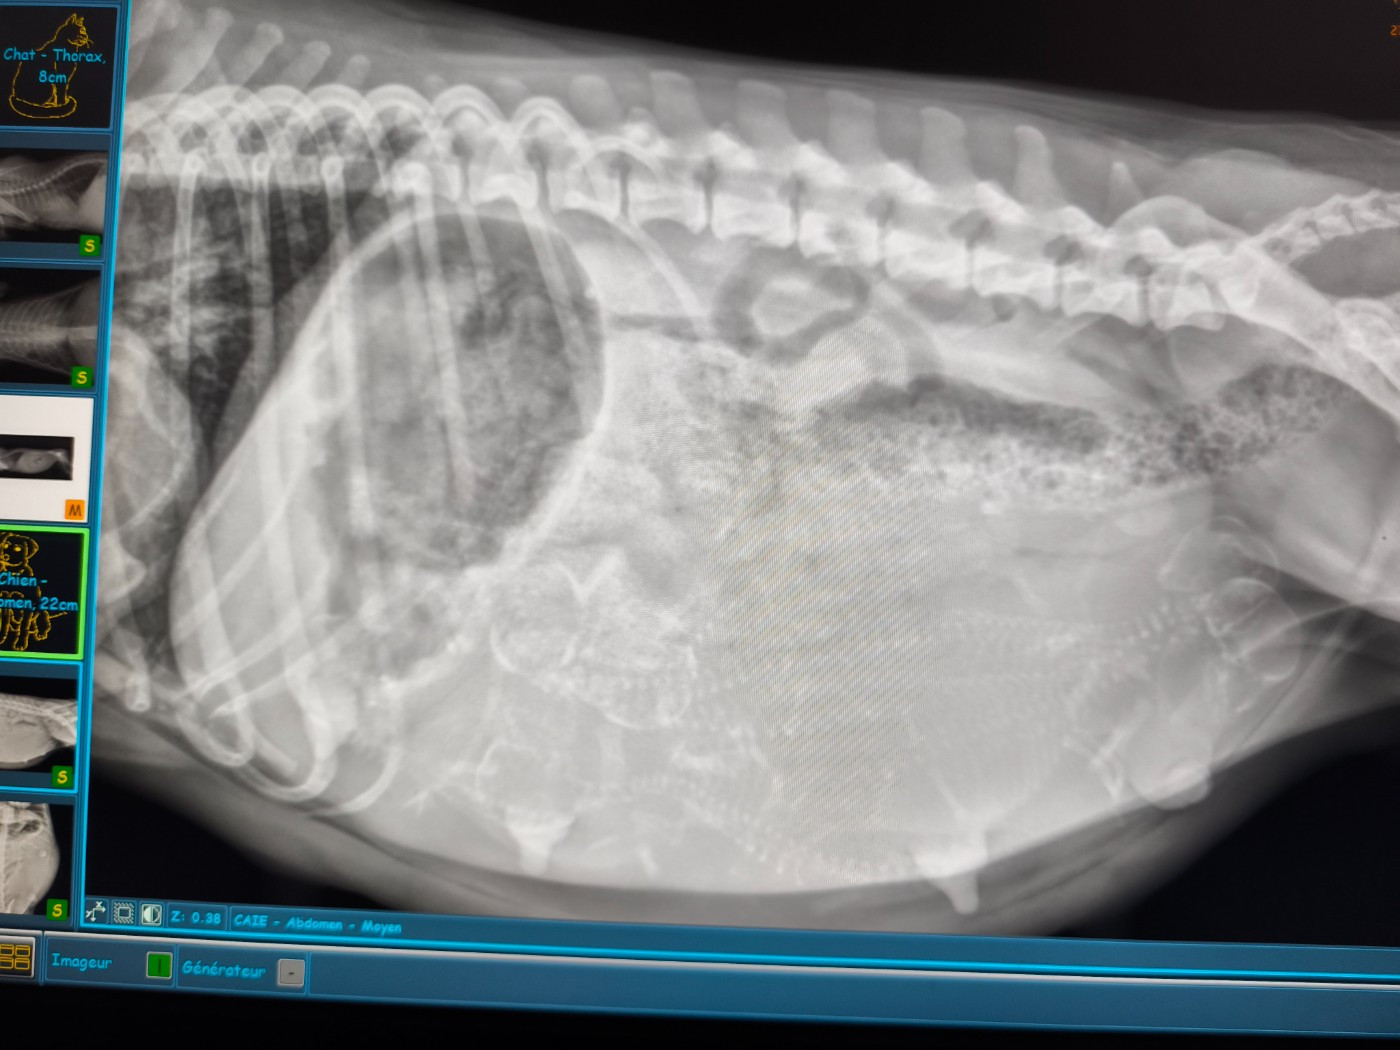

Radio